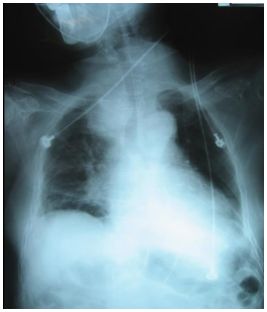

15. 李先生,70歲,罹甲狀腺癌,身體檢查時呈現呼吸喘、急促及窘迫,胸部X光(如附圖), 聽診時最可能發現下列何種狀況?

(A) crackles (B) mediastinal crunch(Hamman’s sign) (C) stridor (D) pleural friction rub